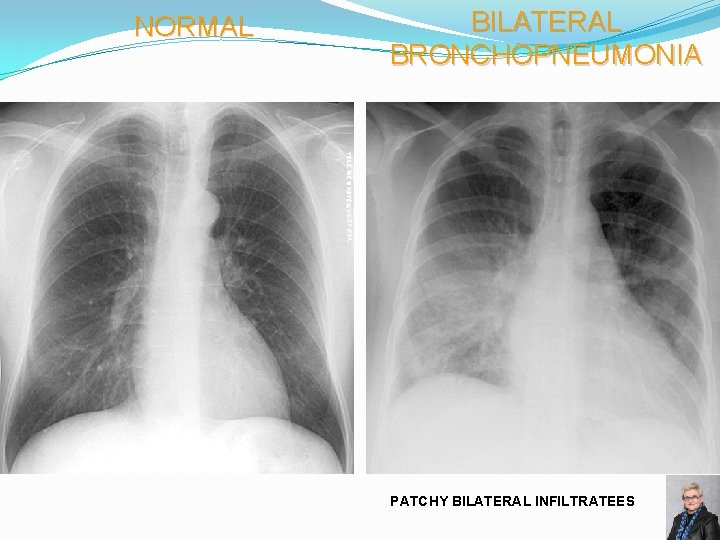

NORMAL BILATERAL BRONCHOPNEUMONIA PATCHY BILATERAL INFILTRATEES 68